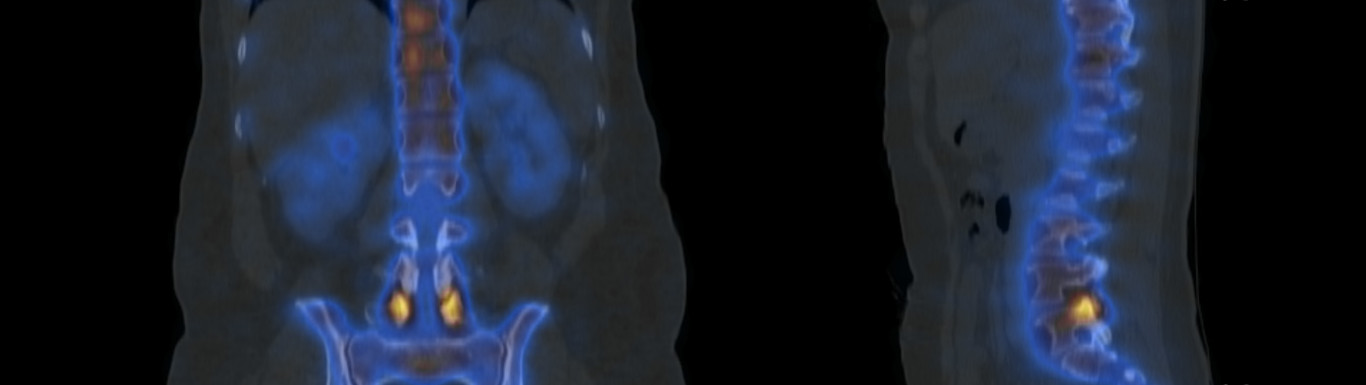

Préparations radiopharmaceutiques et contrôles de qualité

Exploration isotopique de l'appareil ostéo-articulaire

Course categoryDES 2